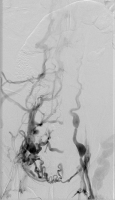

Phlebographie

Abbildung 2: Aszendierende Phlebographie des Patienten mit angiographischem Nachweis der venösen Obstruktion der Beckenstrombahn bds.; ausgeprägter Kollateralkreislauf.